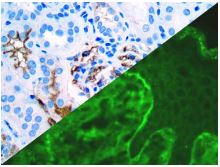

Bio SB has developed a highly sensitive Immunofluorescence and non-biotin monovalent Fab micropolymer IHC detection systems for the detection of IVD antibodies for Complement (C1q, C3c, C3d, C4c, C4d), Serum Proteins (Albumin and Fibrinogen) and Immunoglobulins (IgA, IgD, IgE, IgG, IgM, Kappa and Lambda) related to autoimmune conditions. Our innovative IF and IHC detection systems and high affinity antibodies, have opened the doors for a faster and accurate Immunofluorescence and Immunohistochemistry applicable to Autoimmune Disease like Nephropathies and Lupus.

These antibodies and detection systems are intended for use in Immunohistochemical (IHC) and Immunofluorescence (IF) applications of formalin-fixed paraffin-embedded tissues (FFPE), frozen tissue sections and cell preparations.

Rabbit FluoroDetector FITC |

Rabbit FluoroDetector FITC with FluoroMounter |

Rabbit FluoroDetector FITC with FluoroMounter with DAPI |